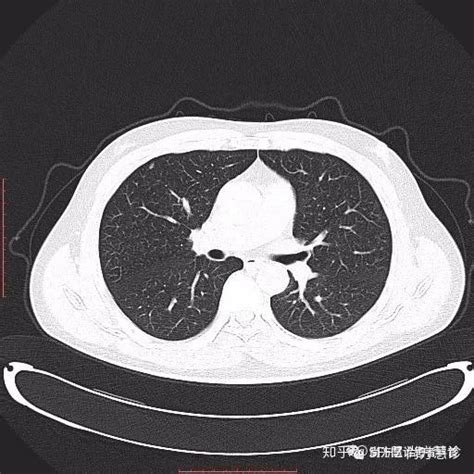

肺结节是指肺部组织内直径小于3厘米的结节性病变,在体检或影像学检查中常常被发现。对于肺结节的诊断和治疗,保险配置起着重要作用。以下是肺结节保险配置的建议和指南: